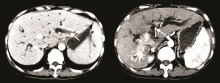

女性患者, 50岁。因“ 确诊肝癌6年余, 身目黄染1周” 入院。患者2007年7月外院体检情况为甲胎蛋白 94.15 ng/mL, B超示右肝实质性占位病变, CT亦示肝占位性病变, 考虑肝癌。2007-07-23我院MRI示:肝S8段占位, 大小为35× 27 mm, 考虑小肝癌可能性大。外科会诊后认为可行肝切除术, 因患者不同意外科手术治疗, 遂于2007-07-26行肝动脉化疗栓塞术, 2007-09-17行无水酒精注入术, 术后CT示S8段病灶内碘油沉积密实。2007年9月至2013年7月(68个月)间规律复诊, 当地医院复查CT示肿瘤病灶稳定。按实体瘤的疗效评价标准评价为疾病稳定。2013年9月外院MRI示肝S8段肿瘤复发, 于2013-09-17行肝动脉化疗栓塞术治疗。2013年10月患者因“ 身目黄染1周” 再次入院。总胆红素369.7 μ mol/L, 结合胆红素180.4 umol/L。2013-10-17我院CT示:肝内外胆管明显扩张, 胆总管上段内见软组织密度肿块影, 大小为25× 26 mm。右肝癌治疗后改变, 考虑右肝后叶肿瘤复发, 肿块累及胆总管且肝内外胆管明显扩张, 见图1。